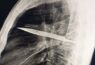

Scan shows knife stuck deep inside a 44-year-old…

[ad_1] According to a case study published in National Library of Medicine on May 31, 2025, a 44-year-old man, who was 'otherwise healthy', sought medical care after his right nipple began leaking pus – and…